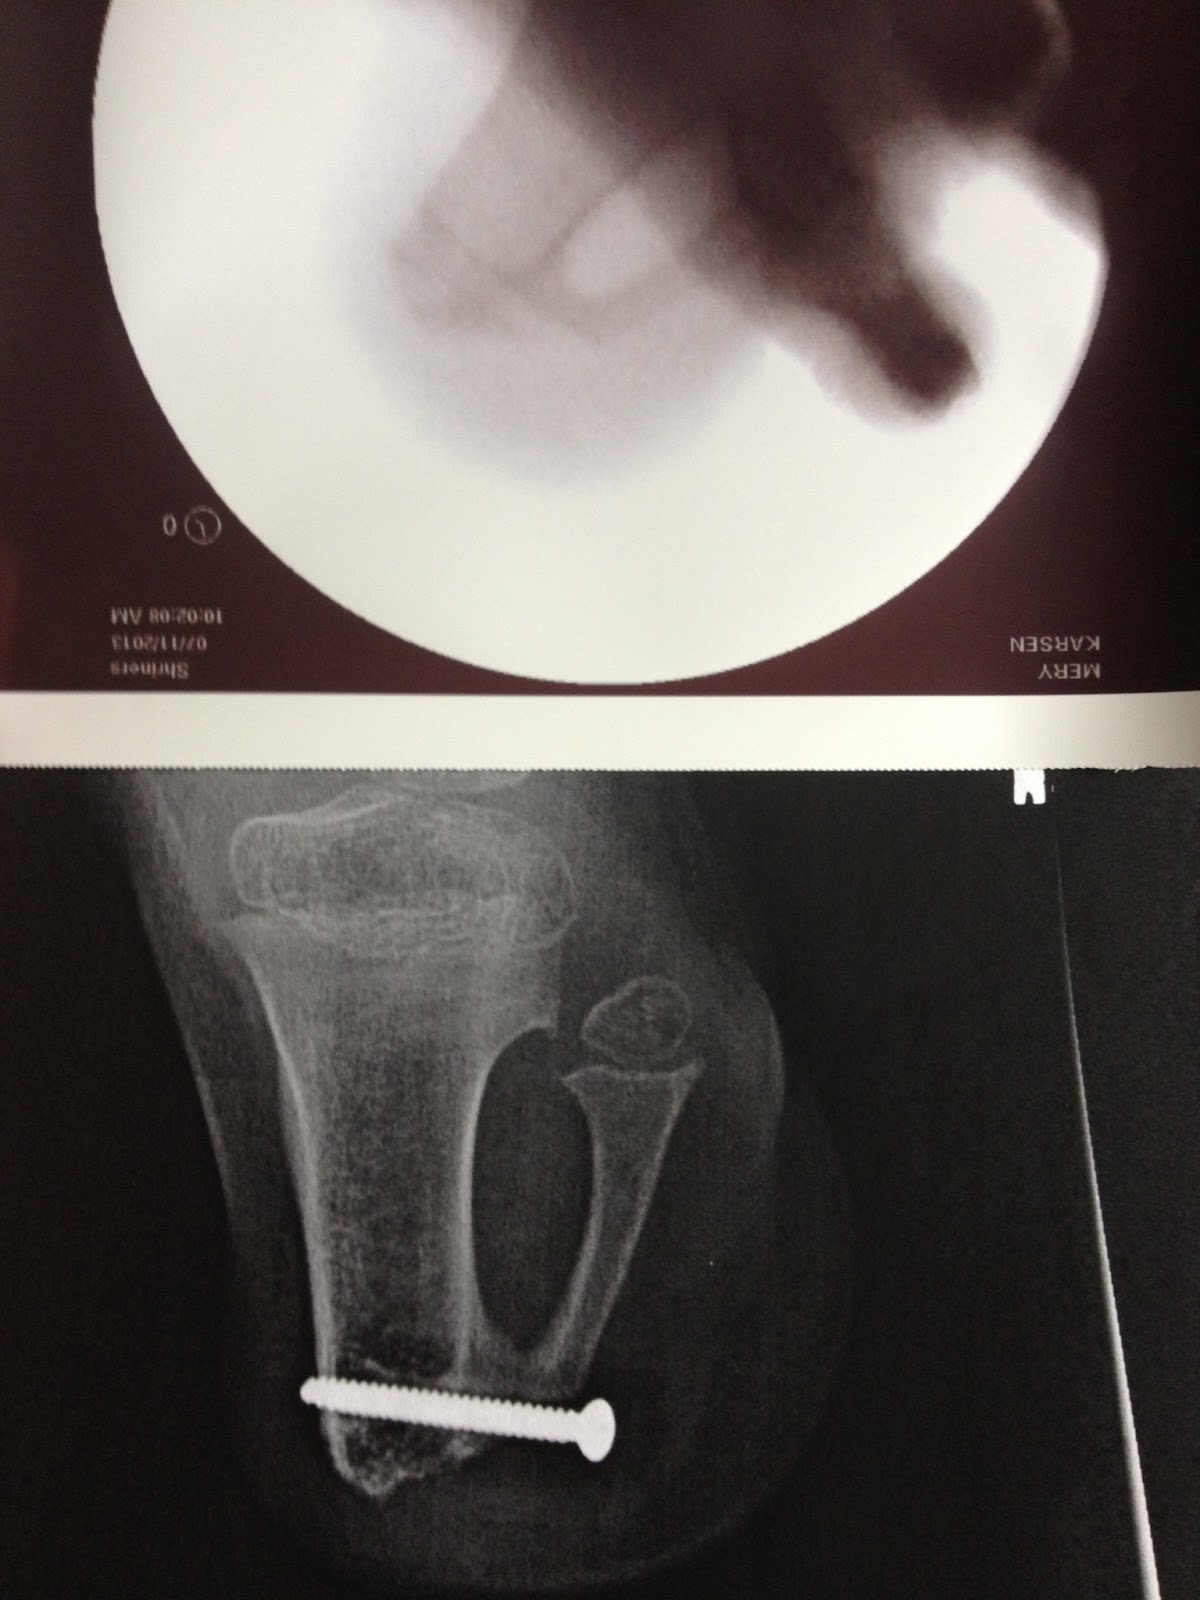

From karsenmery.blogspot.com

Karsen Mery Screw Removal ) Surgery ??? I think we've all lost count Screw Removal Operation removal of implanted metal hardware removal: in order to remove the implant from the bone, there is typically a weakening of the bone. Many foot and ankle procedures require insertion of metal. They do help to hold things in place while the body heals, and they. what is hardware removal after foot or ankle surgery? you've. Screw Removal Operation.